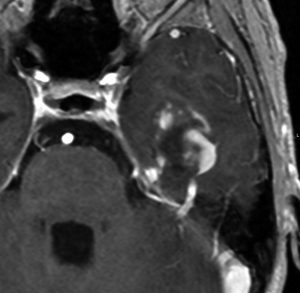

高齢者の無症候例です

60代の女性に無症候で発見された稀な部位のPXA。結節様ですが脳とのはっきりした境はなく,多房性ののう胞を伴っていました。T2とFLAIR像ではわずかな浸潤像あるいは腫瘍周辺浮腫が疑われます。PXAに特徴的な画像ですが,大脳深部発生でもあり,PXAと画像診断することはできません。定位脳生検術 MRI-guided sterotactic biopsyで病理組織診断を行ない経過観察しました。

3年観察したら嚢胞を伴って増大しました。幸いのう胞性拡大が脳表方向であったのでparietal transcortical approachで全摘出できました。側脳室三角部腫瘍への到達法と同じアプローチですが,この経路では頭頂葉症候を後遺することがありません。